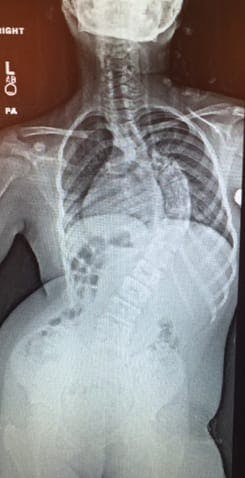

Acquiring high-quality X-rays completely free of charge and being fortunate enough to have Lerman & Sons create a fully custom molded TLSO scoliosis brace for her. Their plan was to send her back to Addis and use the brace as long as they could until she was a little more skeletally mature and ready for surgery.

Yael’s surgery was scheduled and performed by the Hunt brother 4 months later. This surgery was a success. Not only did it greatly lessen the lateral curvature of her spine, but it also increased her performance in day to day activities. This is an email from her father: